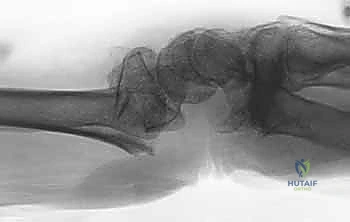

- الأشعة السينية (X-rays):

هي الخطوة الأولى لتقييم الكسر. يتم أخذ صور من زوايا متعددة (أمامية خلفية، جانبية، ومائلة) لتحديد موقع الكسر الأساسي ودرجة الانزياح والتقصير في عظم الكعبرة.

- التصوير المقطعي المحوسب (CT Scan) مع إعادة البناء ثلاثي الأبعاد:

هذا هو المعيار الذهبي الذي يعتمده الدكتور هطيف لجميع كسور المفصل المعقدة. تتيح الأشعة المقطعية رؤية كل شظية عظمية بوضوح تام، وتحديد حجمها، وموقعها، ودرجة تفتت السطح المفصلي بدقة ملليمترية. من خلال إعادة البناء ثلاثي الأبعاد (3D Reconstruction)، يمكن للدكتور هطيف "رؤية" الكسر من جميع الزوايا قبل فتح الجلد، مما يسمح له باختيار الغرسات (الصفائح والمسامير) الدقيقة لكل شظية وتحديد المداخل الجراحية المثلى.